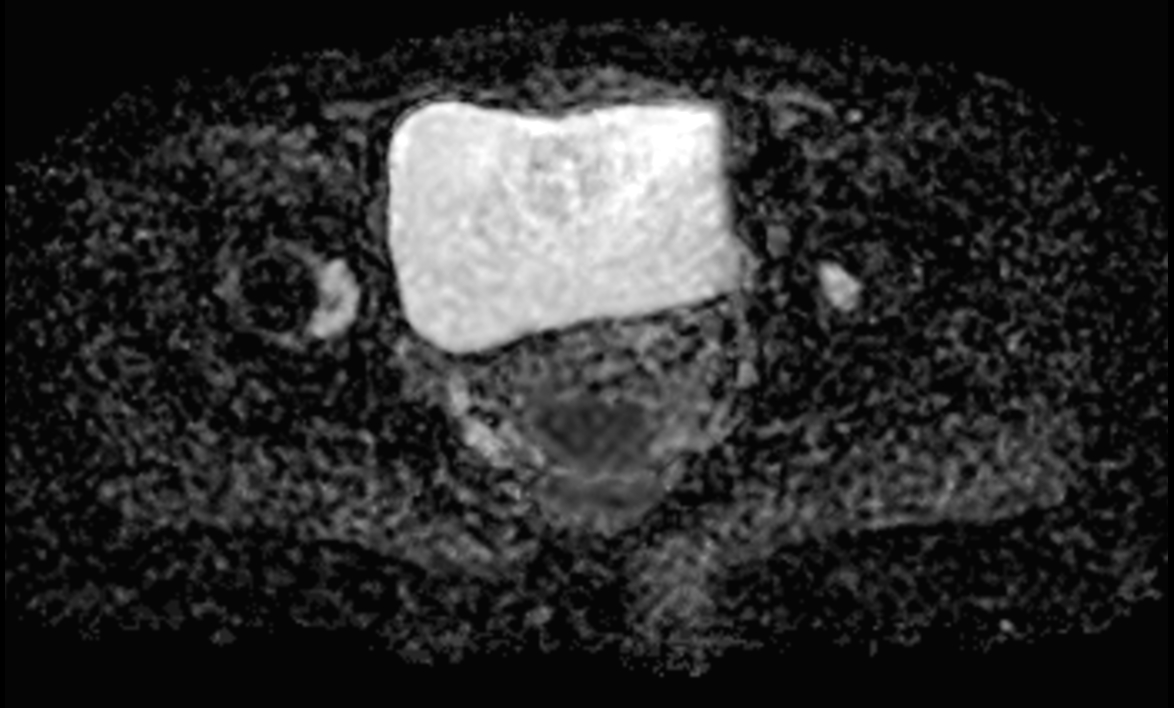

Axial DWI SPAIR (b800) mid

-